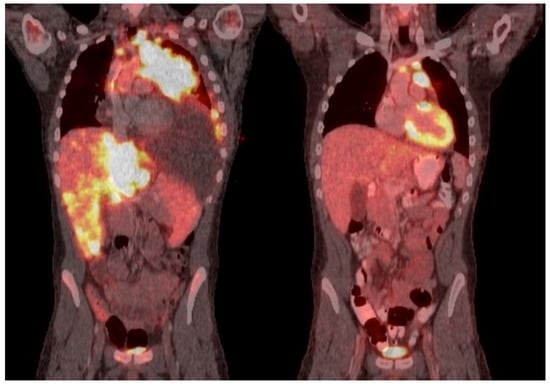

- Baig, M.U.; Rytting, M.; Roth, M.; Morani, A.C.; Nunez, C.; Lin, P.; Cuglievan, B. Venetoclax and Decitabine in Pediatric Refractory T-cell Lymphoblastic Lymphoma. J. Pediatr. Hematol. Oncol. 2021, 43, e991–e996. [Google Scholar] [CrossRef] [PubMed]